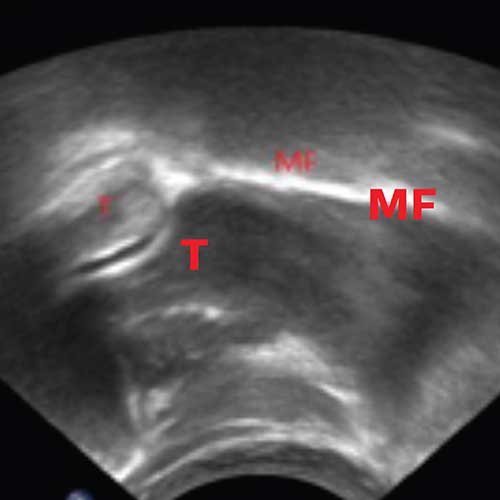

Os requisitos biomecânicos fundamentais necessários para uma alimentação eficaz dos bebés